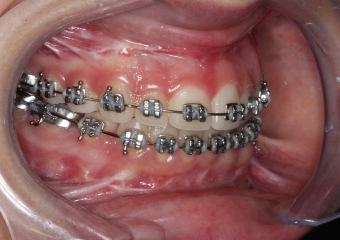

Mordida inicial

Mordida após a cirurgia